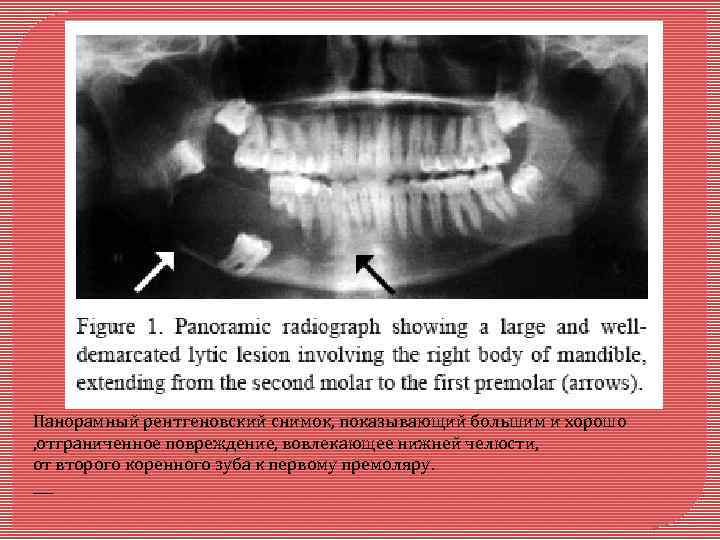

Кальцифицирующая эпителиальная, одонтогенная опухоль Является редкой доброкачественной одонтогенной опухолью, которая составляет приблизительно 1 % всех одонтогенных опухолей. Её происхождение спорно. Кальцифицирующая эпителиальная, одонтогенная опухоль случай запущенной КЭОО, связанной с ретинированным правым вторым моляром в нижней челюсти молодой темнокожей пациентки

Панорамный рентгеновский снимок, показывающий большим и хорошо , отграниченное повреждение, вовлекающее нижней челюсти, от второго коренного зуба к первому премоляру. ___